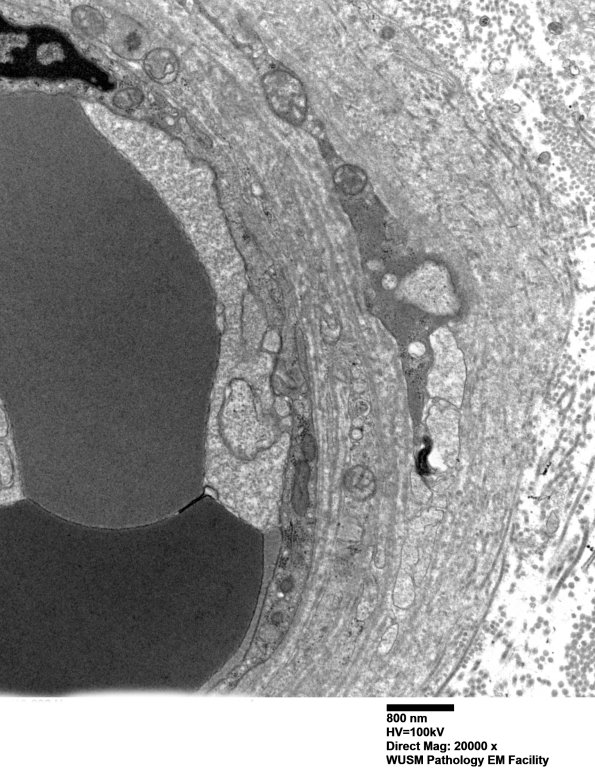

Washington University Experience | VASCULAR | Hypoxia-Ischemia, fetal-neonatal | White Matter | 14B2B (Case 14) EM011 - Copy

14B2B (Case 14) EM011 - Copy